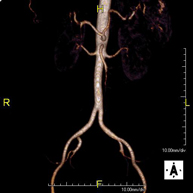

- Lower leg arterial MRI angiography

A non-invasive diagnostic test that involves studying the abdominal aorta, obtaining high-definition anatomical images using an electromagnetic field and radio waves (with transmitter and receiver). The use of paramagnetic intravenous contrast (gadolinium) is essential. However, it is a radiation-free procedure. The quality of the images allows for 2D and 3D reconstructions. It is particularly recommended for patients with suspected vascular disease in both extremities, patients with vascular disease in both extremities as a vascular map prior to treatment (percutaneous or surgical), as a pre-surgical vascular map in patients with bone or muscle injuries requiring surgery, etc.